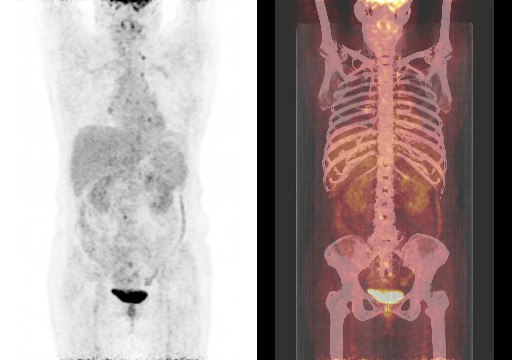

在全球,结直肠癌是发病率位居第三位、病死率位居第二位的肿瘤。肠镜筛查的普及以及手术方式的提升显著降低了结直肠癌的死亡率,但仍有一部分患者在初诊时已发展为晚期,失去手术根治的机会,且预后较差,5年生存率仅12%。许多转移性结直肠癌(mCRC)患者在经历一线治疗后,面临无药可用的困境。近年来,随着靶免联合治疗在系统治疗中逐渐前移,各种靶向治疗药物在mCRC的诊疗中也越发举足轻重。本文分享2例晚期结肠癌患者的诊疗经过,呈现瑞戈非尼在二线治疗为患者带来长生存的治疗价值及其良好的后线应用前景,以期为临床医生提供诊疗借鉴。 病例提供:海军军医大学附属长征医院 王湛 王湛 病例基本情况 一般信息:女 ,58岁。2020年10月,患者无明显诱因出现腹胀,无伴随症状,未予重视。后腹胀进行性加重,2020年11月中旬下腹部隐痛,与进食及体位变化无关,无肩背部放射痛。 辅助检查: 腹部超声:腹腔积液。 腹水脱落细胞病理:腺癌。 腹部增强CT:结肠肝曲癌;腹盆腔积液,腹盆腔腹膜多发转移。 结肠镜(2020-12-4):升结肠近肝曲见隆起型新生物,范围约4cm,新生物表面分叶状,质脆,触之易出血。肠腔狭窄,内镜尚可通过。 2020-12-8病理:横结肠,中分化腺癌,含部分粘液腺癌。 一线治疗2020-12-03至2021-02-24 CAPEOX+贝伐珠单抗 治疗4周期 病情进展,腹胀、腹痛加重,腹水增加。 2021-3-31 PET-CT:腹腔内及腹膜、脾脏、纵隔及右侧心膈角区、左侧锁骨区多发代谢增高灶,结合病史,考虑转移;双肺转移;腹腔及盆腔积液;结肠显示欠清,请结合肠镜检查;双侧胸腔少量积液,左肺下叶部分不张;双肺少许慢性炎症;右肝血管瘤;左肾结石。;子宫术后,痔疮可能;脊柱退变,腰3不稳,腰3/4、4/5、腰5/骶1椎间盘突出。 PFS:3个月 2021-4-6,完善基因检测(腹水标本):KRAS/APC/TERT/TP53/ target=_blank class=infotextkey>P53 突变,TMB 7.98/Mb,MSS 二线治疗,2021-04-02至2021-12 2021-3-31 2021-6-2 2021-8-6肠镜:结肠镜顺利插至回盲部,回盲瓣呈唇状。结直肠粘膜呈桔红色,光滑湿润,有光泽。血管纹理呈树枝状,清晰可见。 PFS:8月 三线治疗,2021-12-13至2022-01-23 三氧化二砷 2021-6-2 2021-11-22 2021-11-22 2022-2-8 PFS:2月 四线治疗,2022-02-10 化疗+免疫+瑞戈非尼+三氧化二砷 2022-2-10开始使用小剂量化疗(雷替曲塞+奥沙利铂+伊立替康)+免疫(信迪利单抗)+瑞戈非尼+三氧化二砷治疗。 疗效评估(2022-9-20):患者病情再次取得缓解。 2022-9-22至今采用维持治疗,降低治疗强度:雷替曲塞 +信迪利单抗+瑞戈非尼+三氧化二砷 2022-9-20 2023-2-8 PFS:13个月+ 该患者为中年女性,诊断为晚期多发转移性结肠癌,基因检测提示KRAS突变,BRAF、NRAS野生型,微卫星稳定,无法进行根治性切除。一线治疗加予CAPEOX联合贝伐珠单抗,治疗4周期后出现病情进展,腹胀、腹痛加重,腹腔积液增加,二线采用瑞戈非尼联合免疫和化疗,患者耐受良好,1周期后腹胀明显缓解,全身状态、PET-CT、肠镜结果较之前明显改善,继续原方案治疗,PFS长达8月。二线治疗进展后完善基因检测,发现TP53 突变,经与患者充分沟通,三线治疗采用三氧化二砷,疗效不佳。四线治疗在三氧化二砷基础上加用瑞戈非尼+免疫+化疗,患者病情再次取得缓解,PFS 超过13个月。近年来,随着精准医学及靶向、免疫治疗的发展,mCRC的管理与治疗策略的制定也变得复杂,合理选择治疗手段、优化全程管理至关重要。本例患者经历了一线化疗联合免疫治疗后疾病出现快速进展,我们个体化地在二线治疗中应用瑞戈非尼联合方案,患者疾病得到控制,PFS 8个月。在四线治疗方案中,再次挑战瑞戈非尼,依然获得较好的疾病控制效果,目前PFS已超过13个月。基于CORRECT和CONCUR研究,瑞戈非尼用于mCRC三线治疗已积累大量临床数据,目前已成为mCRC三线标准治疗方案。此外,REGONIVO、REGOTORI以及RIN方案证实了瑞戈非尼联合免疫治疗MSS型肠癌取得更长的总生存期。一线治疗后疾病进展,能否将瑞戈非尼使用前移,在二线治疗中加用以进一步延长患者生存,以及前线已经暴露过瑞戈非尼,后线再次使用瑞戈非尼是否可行,仍待在临床研究中进一步证实。 02 病例分享二 病例提供:海军军医大学第一附属医院 王薇 王薇 病例基本情况 一般信息:男性,41岁。2020年10月8日,无明显诱因下出现便血,为鲜红色,伴肛门坠胀不适,无排便习惯改变,无腹胀,无消瘦。1997年因“胃溃疡”行胃部幽门切除术;2019年行混合痔手术。 辅助检查: CEA 3.4ng/ml,CA199 3.52u/ml。 当地医院肠镜(2020-11-20):(距肛缘8-10cm)可见粘膜不规则隆起,表面溃烂,易出血。 肠镜活检病理:(直肠)中分化腺癌。 盆腔MRI增强(2020-11-26):直肠中段癌,考虑mrT3N1Mx,MRF-,EMVI-。 肝脏MRI增强(2020-11-27):未见明显异常。 治疗经过 首次手术治疗2020-12-09 腹腔镜辅助直肠癌拖出式适形切除术+末端回肠造口术 术中探查:直肠下段肿物,质硬,未浸润浆膜层,周围系膜未见肿大淋巴结。肿瘤大小约4*4*2cm,占肠腔1/2周,系膜完整。 术后病理: 直肠溃疡型肿瘤大小4.5x3.5x1.5cm;中至低分化腺癌,部分为粘膜腺癌;浸润至外膜层; 癌结节( 3枚+)、脉管癌栓(+)、神经侵犯(+)、肿瘤出芽(+,PDC1级);上下切缘(-)、环周切缘(-)、吻合圈(-);周围淋巴结(2/6),直肠外膜淋巴结(2/4),最高群淋巴结(0/4); 基因分型:KRAS Exon-2 G12D突变,NRAS、BRAF、PIK3野生型;免疫组化:MSH2(+),MSH6(+),MLH1 (+),PMS2(+),pMMR;Ki-67 80%。 术后分期:pT3N2aMx IIIB期 术后辅助治疗(XELOX方案) XELOX方案化疗3周期; 拟行盆腔放疗50gy/25次,2021-03-25起放疗6次 术后复查 肝脏MRI增强(2021-03-27):肝脏多发结节,较前为新发,考虑肝内多发转移瘤 一线治疗,2021-04-22至2021-06-24 mXELIRI+贝伐珠单抗 治疗4周期 患者治疗后出现恶心呕吐,胃纳明显减退,Ⅱ°粒细胞下降,腹泻,脱发,轻度手足皮肤反应,手足冰凉,心悸。患者无法耐受继续治疗 维持治疗,2021-7-15至2021-8-26,卡培他滨+贝伐珠单抗,共计治疗3周期 肝脏MRI增强(2021-5-31、2021-8-24):肝右后叶上段7mm小结节灶,转移不除外,腹膜后稍大淋巴结较前相仿,随访。 2021-3-27与2021-5-31的肝脏MRI增强对比图 2021-8-24 肝脏MRI增强 盆腔MRI增强(2021-8-25):术区及骶前软组织肿胀,左侧条索影,结合CT考虑术区置管术后改变,较2021-06-01片大致相仿。 疗效评估:PR 后患者诉心悸、乏力、胃纳不佳;血压正常;心肌酶正常;心脏彩超LVEF 64%;EKG: 窦性心率,T波低平;尿蛋白(-)。患者对化疗非常抗拒。 二线治疗,2021-09-17至2021-12-15 盆腔MRI增强(2022-9-13):术区及骶前软组织肿胀,左侧条索影,结合CT考虑术区置管术后改变,较前片大致相仿。 胸部CT(2022-9-13): 右肺下小结节,随访。 疗效评估:PR。 2022-12-20肝脏MRI增强:平扫+增强未见明显异常。 2022-12-21盆腔MRI增强:直肠癌术后,盆腔区未见明显复发及转移病灶。 病例总结 该患者为中年男性,诊断为局部晚期直肠癌,原发灶术后分期IIIB期,基因检测KRASExon-2G12D突变、微卫星稳定。术后仅3月余在XELOX方案辅助化疗、盆腔放疗期间出现多发肝转移,疾病进展转移灶不可切除,进而接受XELIRI方案联合贝伐珠单抗二线全身治疗。治疗后肝脏多发转移瘤退缩理想,病灶明显缩小减少。但患者治疗副反应不可耐受,改卡培他滨联合贝伐单抗治疗后持续有效,但仍无法耐受副反应。遂予以瑞戈非尼靶向治疗:120mg日剂量口服,服用三周停用一周至今。患者耐受良好,近期复查未发现明显复发转移病灶。目前二线PFS已达23个月,瑞戈非尼二线维持治疗DoR17个月。目前,二线治疗在不同患者亚群的优选方案仍存在争议。而整个系统治疗到了三线阶段,标准治疗主要价值是能够延长患者的疾病控制时间,缩瘤效果和客观缓解率均不理想,并没有满足目前的治疗需求。根据目前的药物机制和临床研究结果,考虑到患者的具体情况:涵盖治疗目标、体质状况、对预估的不良事件的耐受性及是否存在相关危险因素、既往治疗用药情况等方面,我们采用了个体化的瑞戈非尼二线维持治疗方案取得良好疗效,这种治疗策略希望能在规范临床研究中证实。病例分享一